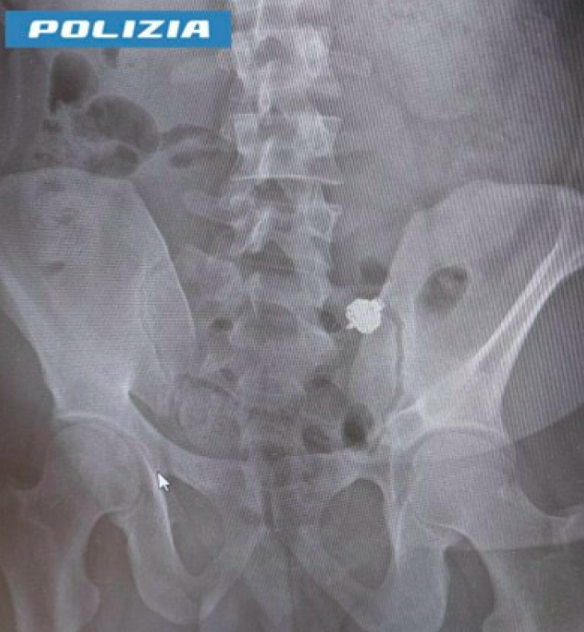

Una storia incredibile, ma reale. Ha ingoiato l’auricolare, quando si è visto scoperto mentre imbrogliava all’esame di teoria per la patente. È accaduto nei giorni scorsi a Bolzano all’Ufficio patenti della Provincia autonoma. In aula erano presenti agenti in borghese della Polizia che hanno sorpreso una persona con un microauricolare inserito in un orecchio, verosimilmente utilizzato per farsi suggerire le risposte.

Nella speranza di distruggere la prova a suo carico, il candidato ha ingoiato il supporto tecnico. Il candidato è stato così accompagnato al Pronto soccorso e sottoposto ad una radiografia che ha mostrato la presenza dell’auricolare. È scattata la denuncia per i reati di presentazione di esami opera di altri (una vecchia ma ancora efficace legge del 1925) e per falsità ideologica per induzione, fatti per i quali rischia la pena della reclusione da 6 mesi a 2 anni.